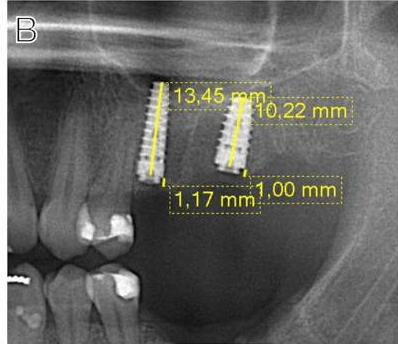

Case photo below provided by: Sharma K, Aggarwal S, Gupta K, Madan R, Tariq S, Narula IS, Gupta S. Three-Dimensional Evaluation of Alveolar Bone Levels Around Dental Implants and Natural Teeth: A Prospective Study.

Evaluation of the marginal bone loss: (A) Buccal and lingual aspect of natural tooth, (B) mesial and distal aspect of natural tooth, (C) buccal and lingual aspect of dental implant, (D) mesial and distal aspect of dental implant.

This study concluded that:

Based on the findings of the present study, it was concluded that the mean marginal bone loss and probing depth( PD) were higher on the implant side than on the natural contralateral tooth during the 18-month follow-up period, and it was the highest on the distal side. Bone loss and PD were higher at the 18-month follow-up than at the six-month follow-up. The duration between the first- and second-stage implant surgery and PD were two significant predictors of bone loss at the mesial and distal sides of the implant. Age and sex were not significantly correlated with bone loss in any of the regions.